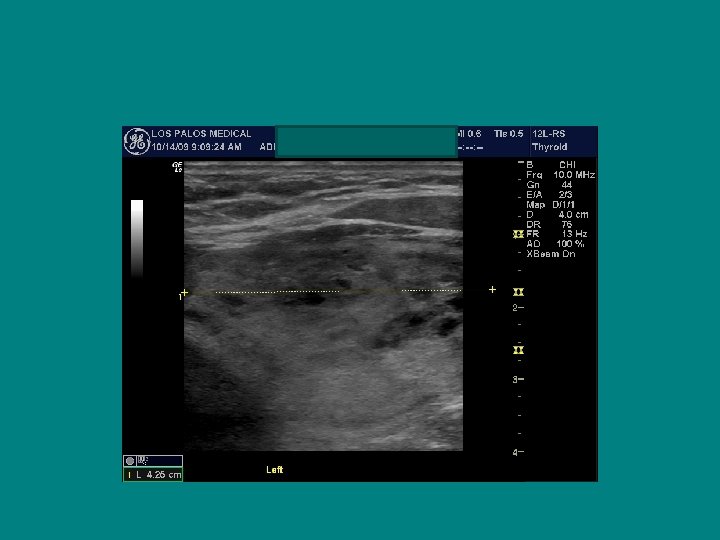

Right Left

Normal TSH with Irregular gland